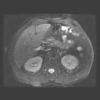

Abdomen